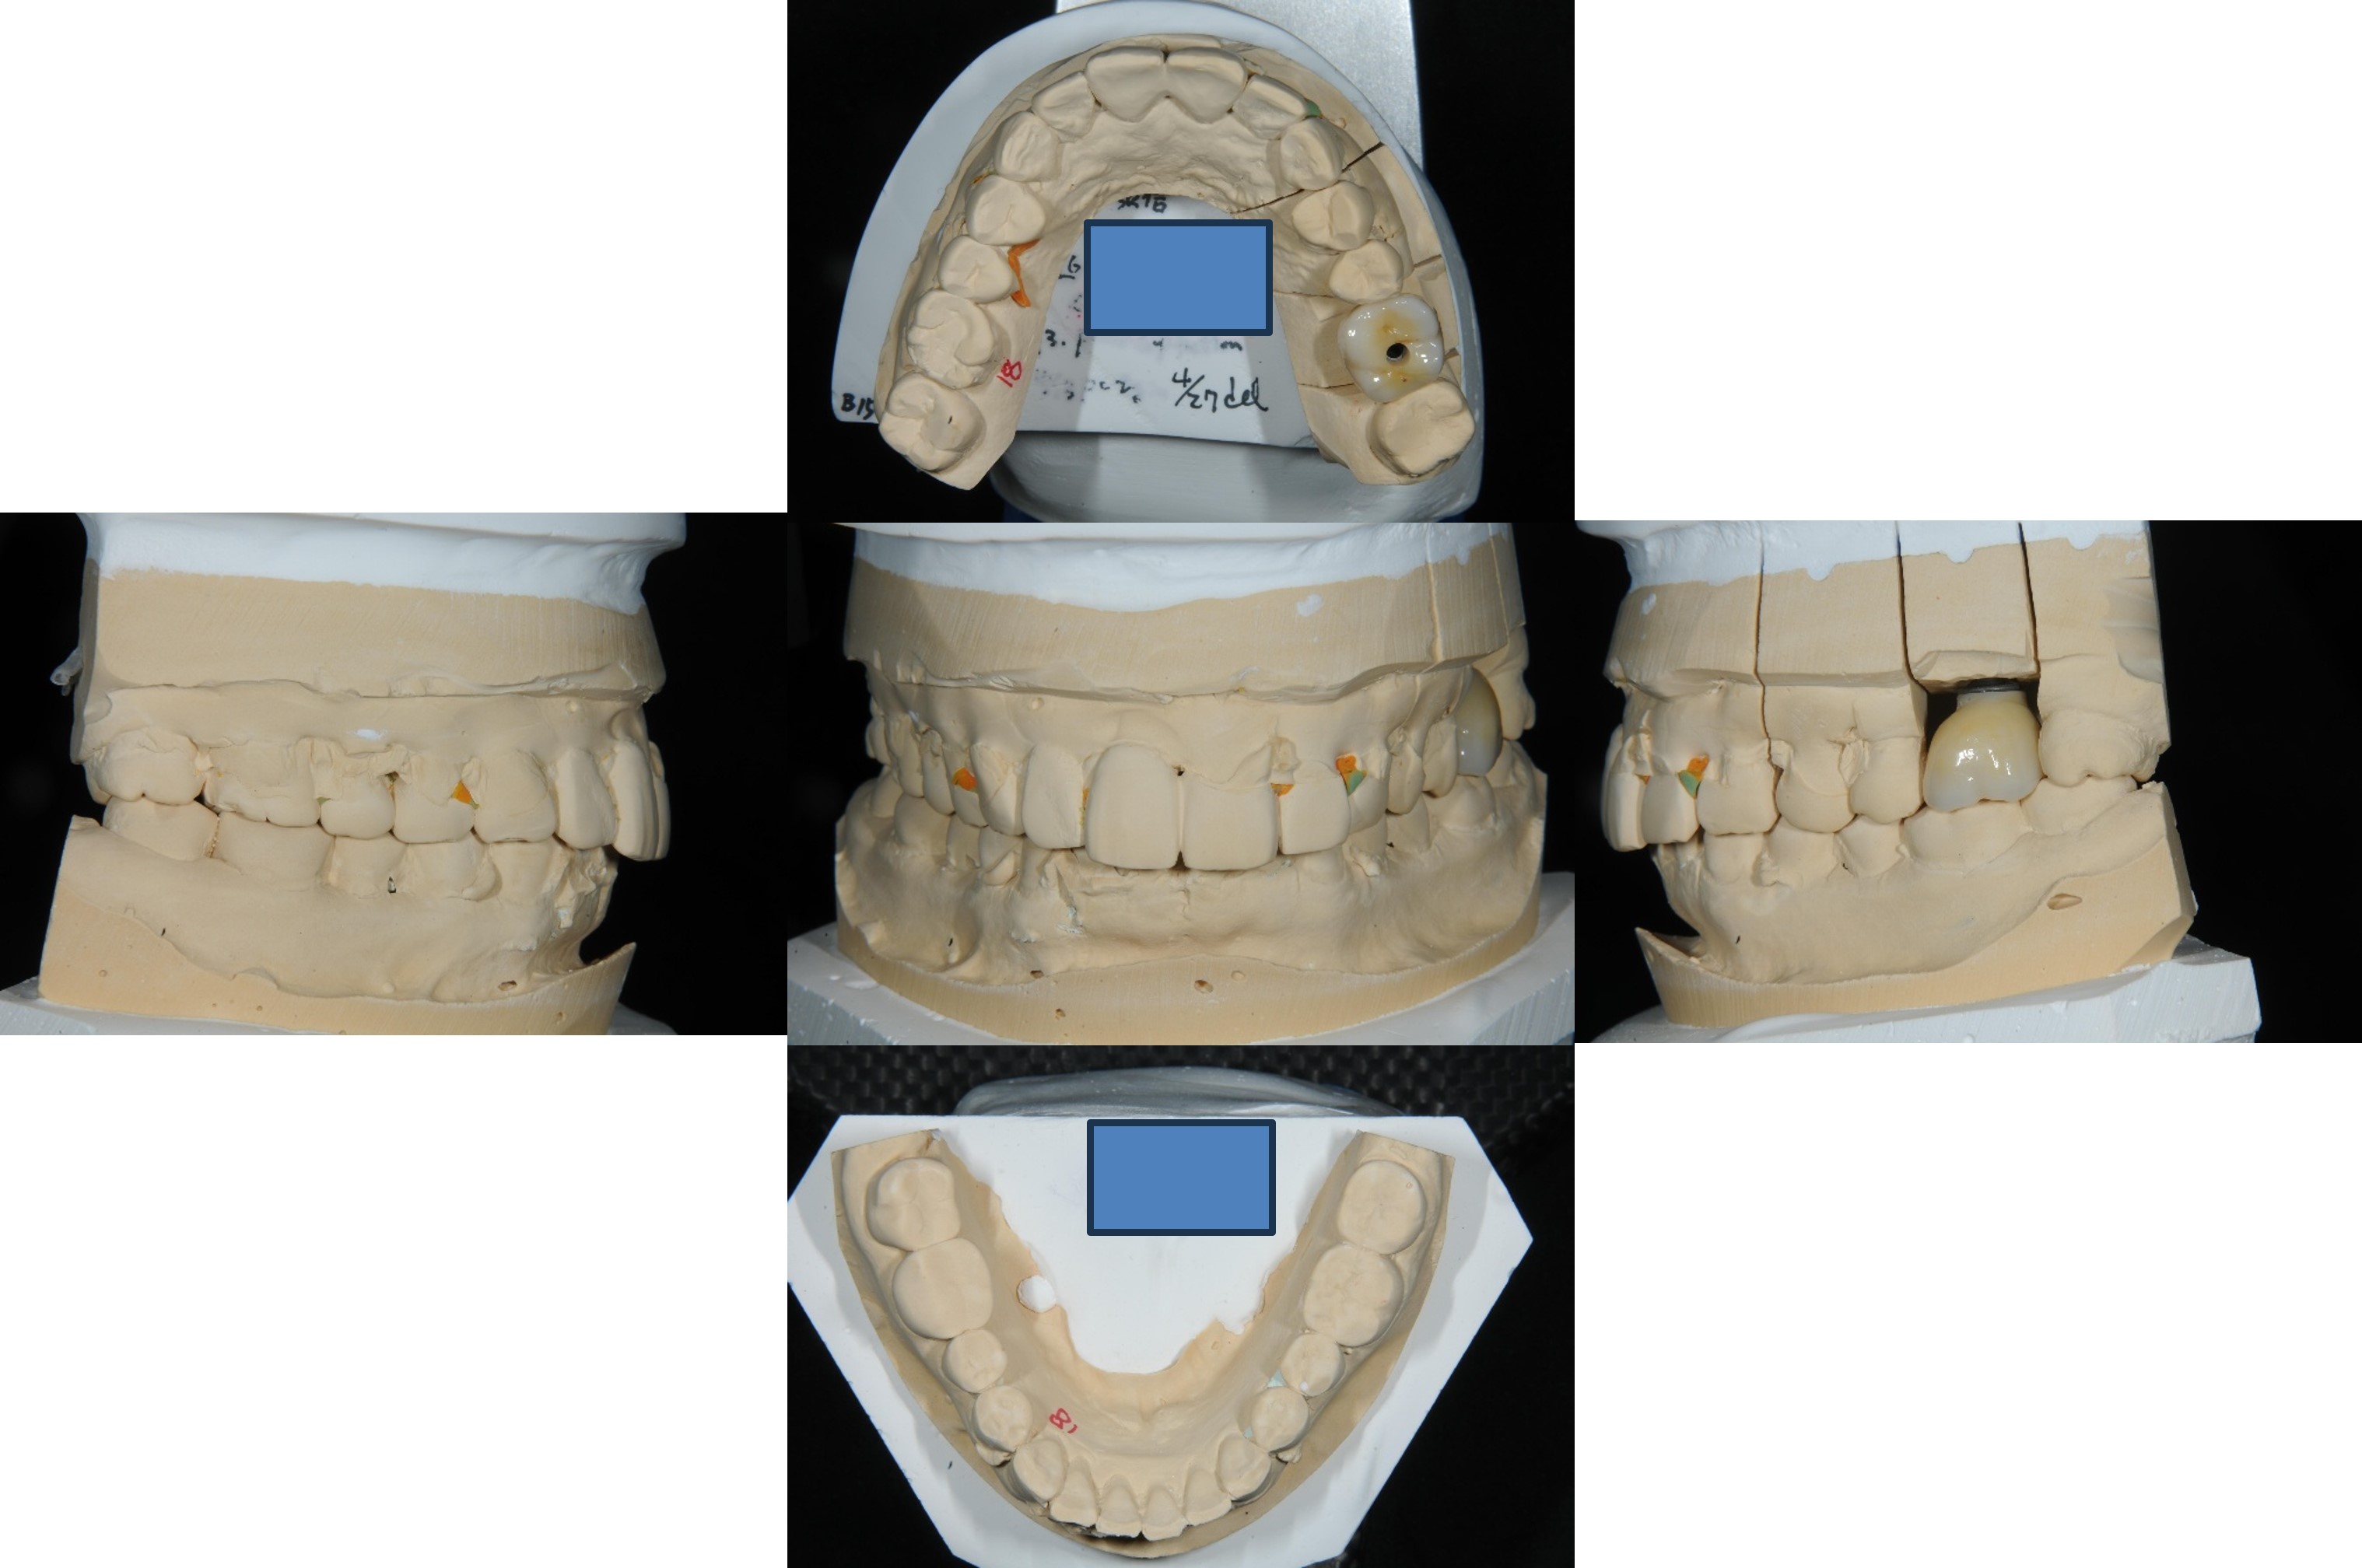

面弓轉移,上咬合器

咬合器上製作瓷牙